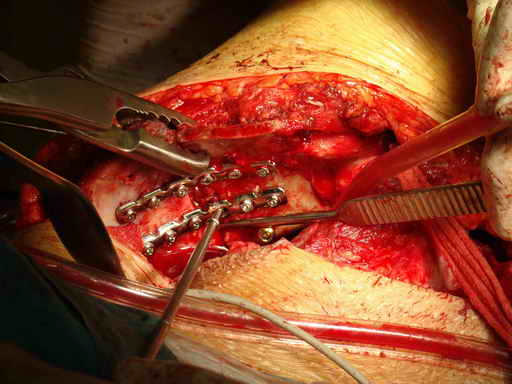

Остеосинтез подвздошной кости

Укладка тазовой пластины "matta"

Операционная. Оперирует д.м.н. проф. Казанцев А.Б.

уважаемый доктор Атом.....Вам не кажется доступ слишком кровавым и травматичным. ведь осуществляемый вами хирургическицй доступ утяжеляет состояние больного, а кровоточащие сосуды спина илиака увеличивают кровопотерю. А как же хронический ДВС синдром на фоне вашего вмешательства? РО - картина не очень, есть видимость винтов во впадине и ещё какова длительность, столь неоправдано большой операции? Покажите послеоперационную рану? Какие антибиотики вы используете? Время открытой раны?

Уважаемый коллега, не стоит строить утвердительные предложения с выражением "Вам не кажется". Данный хирургический доступ применяется около 8 лет. Помимо того что создаются благоприятные условия для репозиции, сокращается время операции и как следствие - уменьшается кровопотеря, которая составляет около 1 л. при свежих случаях. При застарелых же, по очевидным причинам, существенно выше. Максимальная кровопотеря была 5450 мл. у больного после спленэктомии и давностью травмы более 1 года. Была выполнена одномоментная реконструкция таза с протезированием тазобедренного сустава. Пользуемся Cell Server-ом, производим аутозабор в предоперационном периоде, возвращаем дренажную кровь. ДВС? Тьфу, тьфу, тьфу! Это заслуга АРО и трансфузиологов, и именно они нам позволяют выполнять такие вмешательства.